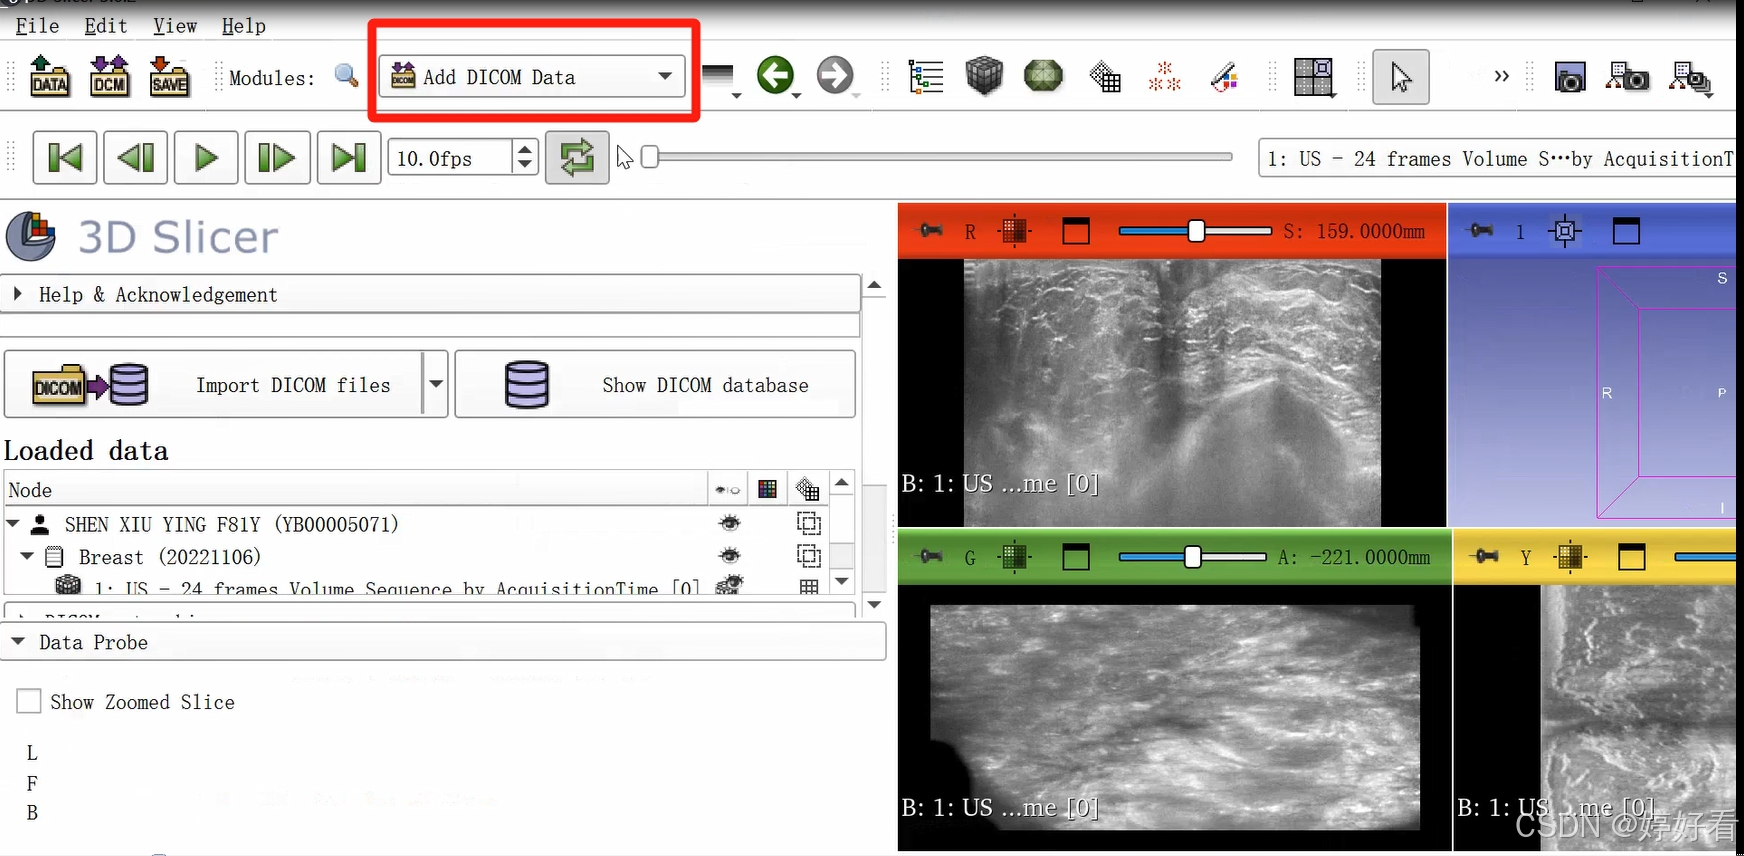

2、病灶分割

2.1 首先,点击以下图片中的下拉箭头,然后选择Segment editor。